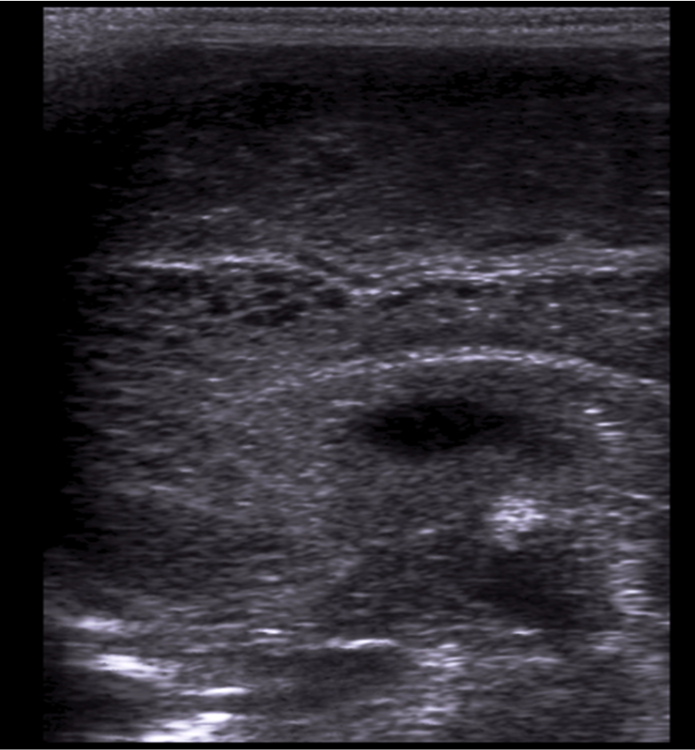

Neonatology Grade 2 PVL 2 Image